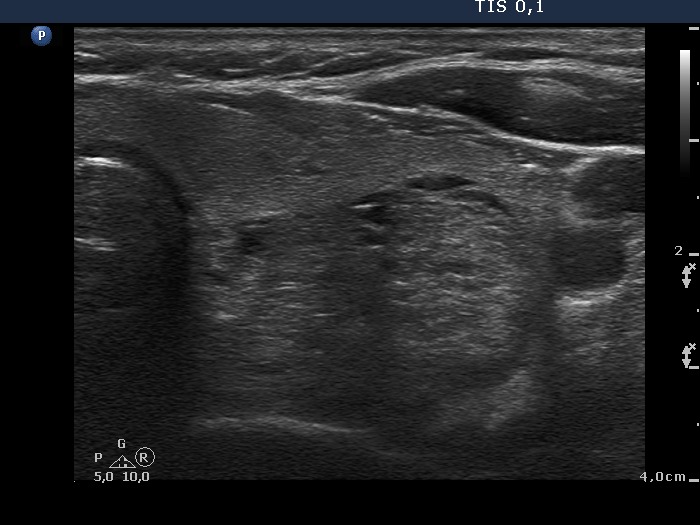

Ultrasonography: the thyroids were echonormal. There was a small hypoechogenic lesion in the ventral part of the right lobe, while a large hyperechogenic nodule presenting a halo sign and perinodular blood flow in the left thyroid. The size of the nodule increased from 25x19x27 mm to 30x27x33 mm (width, depth, length, respectively).